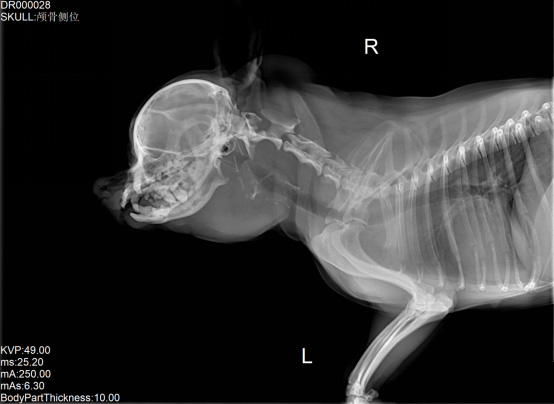

寵物DR數(shù)字化X射線檢查技術(shù)提高寵物醫(yī)生工作效率

寵物DR是專業(yè)用于寵物X光拍攝的數(shù)字化X射線檢查,輔助寵物醫(yī)生進行及時精確的診療。寵物DR主要包括五大主要部件,數(shù)字X光探測器,高壓發(fā)生器,球管,機架,寵物專用的DR工作站軟件。寵物DR由于采用數(shù)字技術(shù),自動成像處理,模擬X線圖像向數(shù)字化X線圖像的轉(zhuǎn)變。寵物DR與傳統(tǒng)模擬X光機相比有什么優(yōu)勢呢?采集時間10毫秒以下,成像時間僅為3秒,較高的空間分辨力和低噪聲率,提高了病灶的檢出率,避免漏診誤診等問題。減少X線對人體照射的不良影響寵物DR照片是您最佳的選擇。提高寵物醫(yī)生工作效率,總而言之,選擇寵物DR是寵物醫(yī)院的最佳選擇。寵物醫(yī)學影像學實現(xiàn)全數(shù)字化和無膠片化升級發(fā)展提高技術(shù)水平。